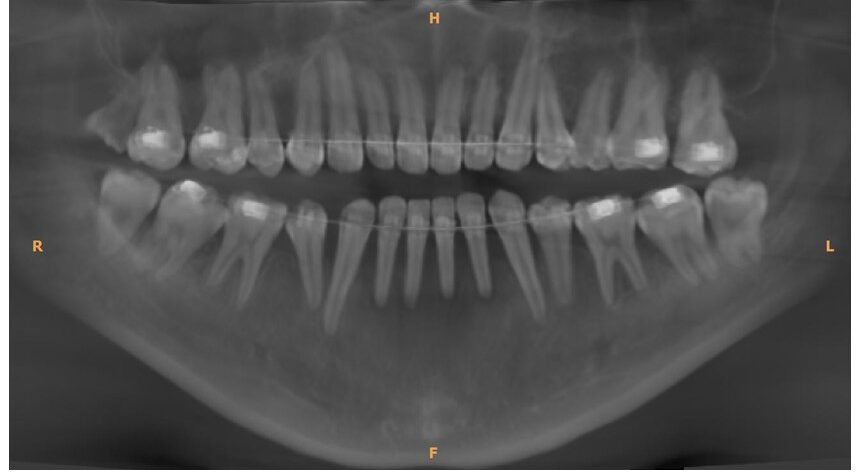

前回1月18日に歯石取りなどを終えており、歯茎の状態も特に悪化していることもなかったので、2月21日にレントゲン検査 (CBCT) 実施後、2月28日と3月28日に歯肉移植手術(下の歯左右2番と3番計4本に対し、左側と右側の2回に分けて行う)を実施することになりました。

・2026年2月21日撮影

2026年2月21日(土)

Audy Dental Kemang:Rp. 1.765.000 (14,120円)

・レントゲン検査(Rontgen CBCT):Rp. 1.700.000

・その他(Administrasi):Rp.65.000